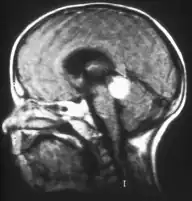

Inherited forms of retinoblastomas are more likely to be bilateral. In addition, inherited uni- or bilateral retinoblastomas may be associated with pineoblastoma and other malignant midline supratentorial primitive neuroectodermal tumors (PNETs) with a dismal outcome; retinoblastoma concurrent with a PNET is known as trilateral retinoblastoma.[17] A 2014 meta-analysis showed that 5-year survival of trilateral retinoblastoma increased from 6% before 1995 to 57% by 2014, attributed to early detection and improved chemotherapy.[18]

Aspect of trilateral retinoblastoma on MRI -

Traditional ultrasound B scan can detect calcifications in the tumour while high-frequency ultrasound B scan is able to provide higher resolution than the traditional ultrasound and determine the proximity of the tumour with front portion of the eye. MRI scan can detect high-risk features such as optic nerve invasion; choroidal invasion, scleral invasion, and intracranial invasion. CT scan is generally avoided because radiation can stimulate the formation of more eye tumours in those with RB1 genetic mutation.[37]